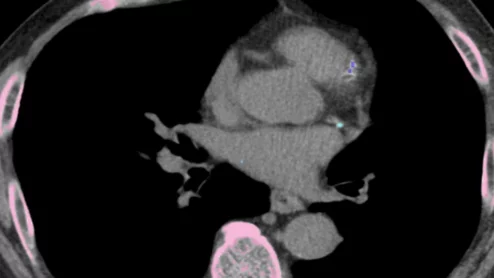

long covid lung CT

The statement is intended to standardize terminology, indications for CT use, acquisition parameters and reporting guidelines for patients with long COVID.